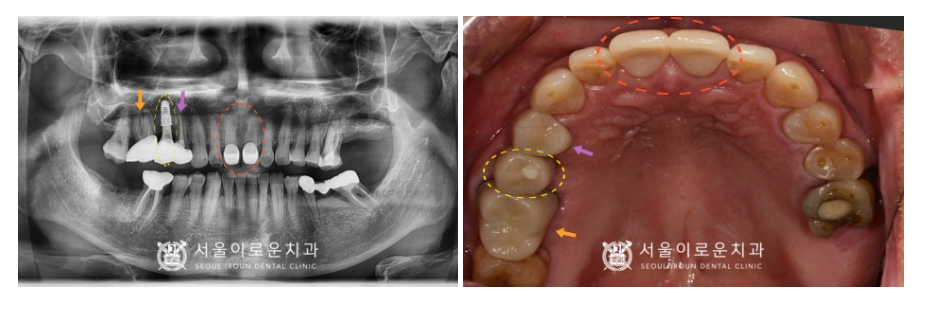

노란색 동그라미의

오른쪽 위턱 두 번째 작은 어금니(#15)의

뿌리 주변으로 잇몸뼈가

많이 흡수되어 있었으며,

충치도 심한 것을 확인할 수 있었습니다.

이 경우 살려 쓰기 어려울 것으로 판단되어

안타깝지만 발치가 필요한

상황이었습니다.

그리고 보라색 화살표의

오른쪽 위턱 첫 번째 작은 어금니(#14) 또한

통.증을 호소하셨는데요.

충치가 치아의 허리 부분에 해당하는

치경부 깊이 진행되어 있어

신경치료 후 크라운 치료가 필요하였습니다.

또한 주황색 화살표의

오른쪽 위턱 첫 번째 큰 어금니(#16)는

예전에 신경치료까지만 진행이 되어있고

크라운 수복을 하지 않은 상태였는데요.

그렇다 보니 레진 경계부에

이차우식이 진행되어

크라운 치료가 필요하였습니다.

그리고 마지막으로

환.자분께서 말씀하셨던

빨간색 동그라미의 앞니(#11,12)

충치 부분은

그냥 육안으로 보기에도

두 개의 치아 사이에

까맣게 충치가 생긴 것을

확인할 수 있었는데요.